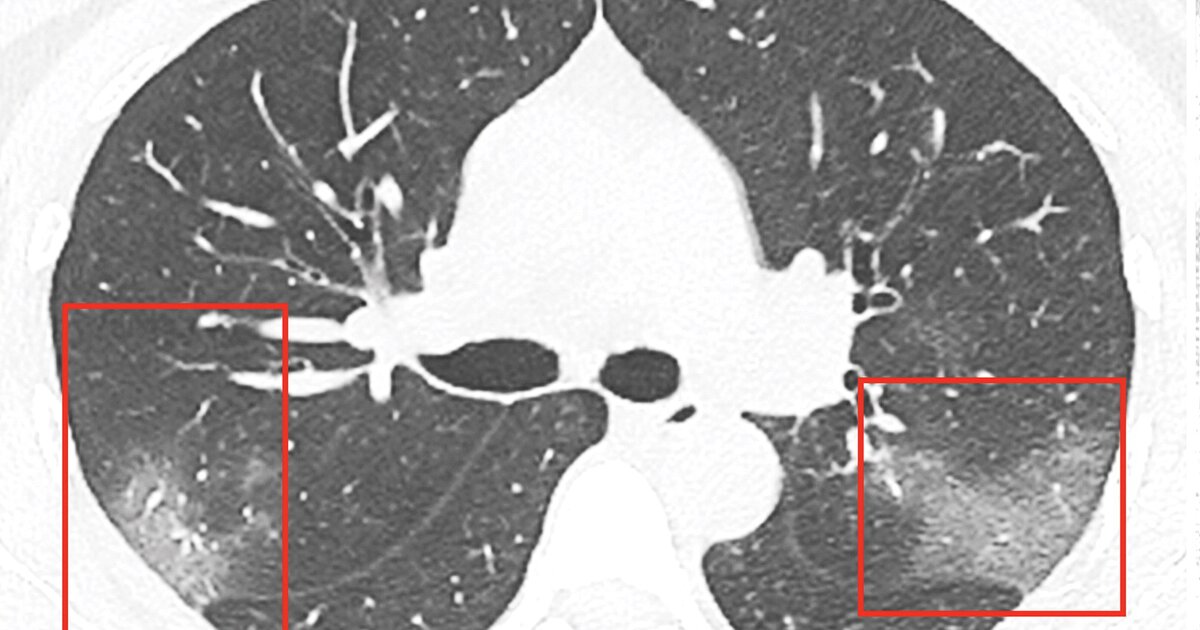

Можно ли определить коронавирус по снимку легких - фото презентация